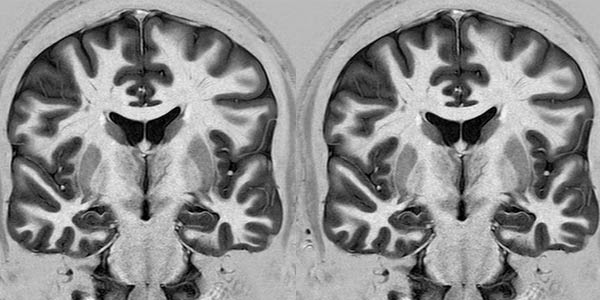

Ilmuwan dari Oxford University, Inggris, memindai otak koresponden saat mereka memilih salah satu kotak untuk memenangkan sebuah hadiah. Mereka akan diberi saran namun saat mereka diberi informasi bohong, tingkat aktivitas dari dorsomedial prefrontal cortex (DPFC), area di depan otak, akan meningkat secara drastis.

Aktivitas itu menunjukkan betapa informasi bohong dapat menyebabkan reaksi pada otak sehingga mempengaruhi prediksi seseorang. Kegagalan pada sistem ini dapat menjelaskan mengapa seseorang yang mengalami schizophrenia lebih sering merasa paranoid.